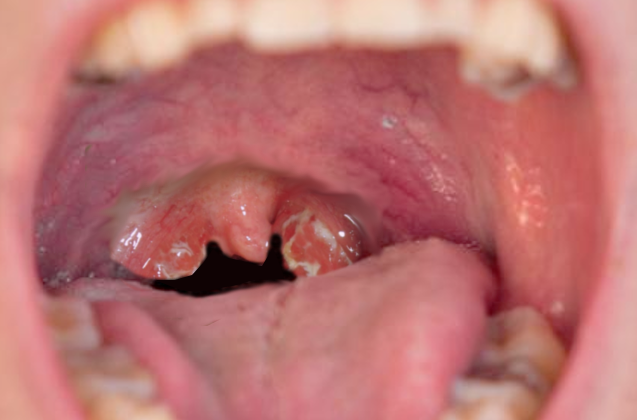

• تضخم اللوزتين: الظاهر بانتفاخ واضح في منطقة الحلق.

• احتقان في الحلق وصعوبة في التنفس: نتيجة التضخم أو وجود لويحات قيحية.

1. الفحص السريري: بواسطة الطبيب، حيث يتم فحص الحلق واللوزتين للبحث عن تضخم أو لويحات قيحية أو تجاويف.